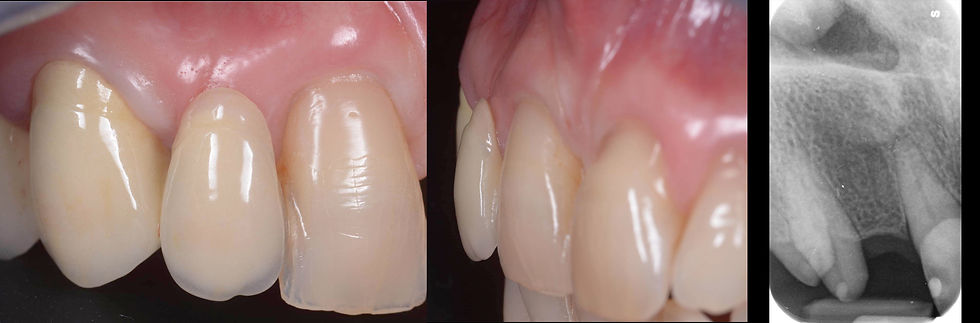

Lateral and radiographic details of the element 1.2.

Occlusal view of the element 1.2. The depression of the vestibular prominence is evident, due to the natural rearranging of the edentulous area.